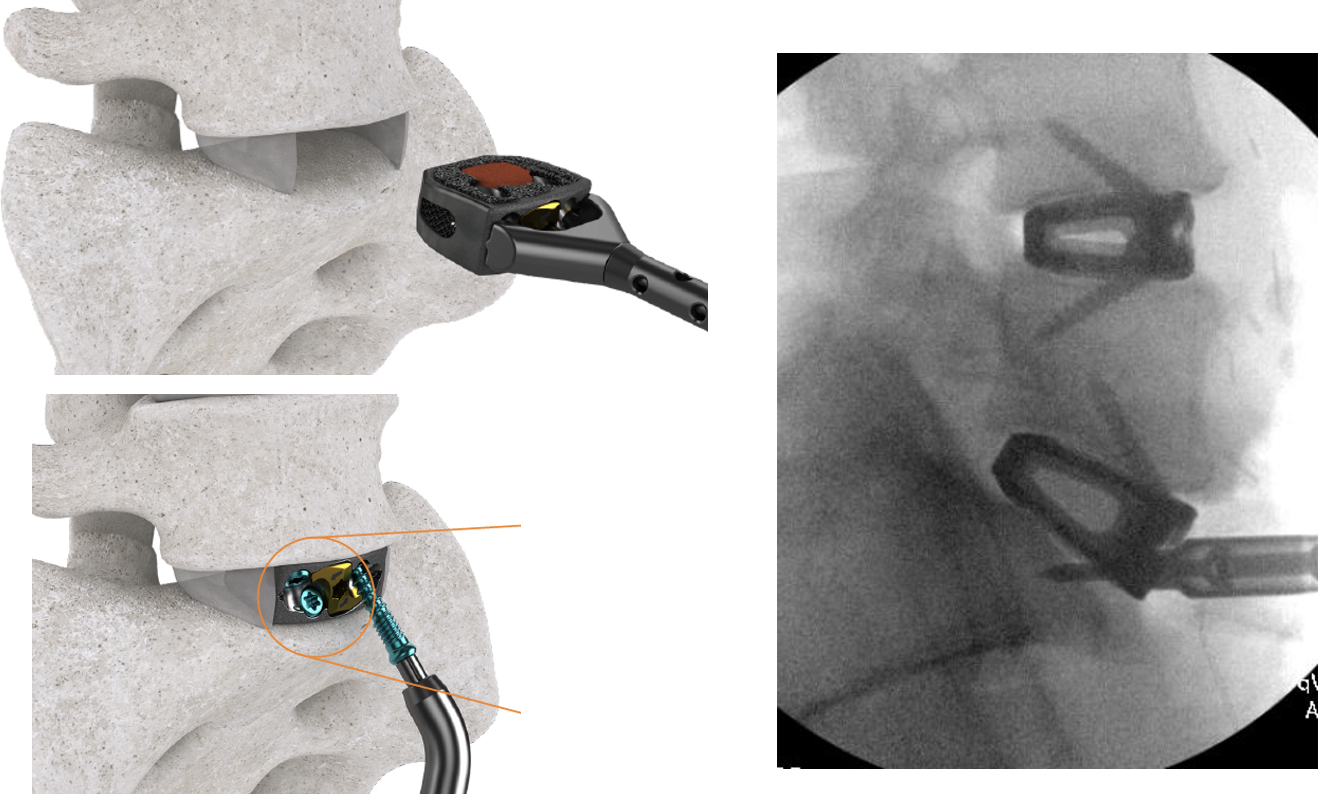

Lateral (Side) Procedure: XLIF (also called LLIF)

- You will be positioned lying on your side.

- XLIF is done through a one inch incision that is made on the side of your abdomen between the ribcage and the pelvis.

- A series of tubes (dilators) are placed through the incision, one over the other through the muscle tissue onto the bones of the spine.

- A tubular retractor is placed over the dilators which are then removed. The tubular retractor is typically the diameter of a half-dollar and serves as a working channel or portal that the surgeon can perform the surgery through, leaving the muscle tissue intact. This minimizes incisional pain and scarring of the muscles.

- Special instruments are used to work through the tube to remove the painful, degenerated disc and bone spurs (excess bone growth due to arthritis) to take pressure off of the nerves.

- The degenerated disc is then replaced with a fusion cage made of either a special plastic called PEEK or titanium and filled with bone graft.

- The retractor is removed, and the incision is closed with resorbable stitches that are placed beneath the skin.

- Typically, for the A.L.P. fusion, the LLIF will be performed at L2-3, L3-4 and L4-5.